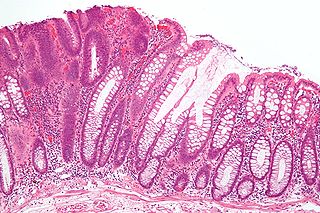

סרטן המעי מתחיל בפוליפים או גידולים קטנים בדופן המעי, ומתפתח בארבעה שלבים, שבראשונים שבהם אין בדרך כלל סימפטומים. בשלבים מתקדמים יותר יכולים להופיע כאבי בטן, שינויים ביציאות, דימום בצואה, ולעתים חסימת המעי. הדימום אינו קבוע והוא קיים בצורה סמויה ולא מורגשת גם בשלבים הראשונים, לפני שמופעים סימנים אחרים.

תצלום של פוליפ (משמאל) במעי הגס המבשר את סרטן המעי הגס | תמונה: Nephron, wikipedia